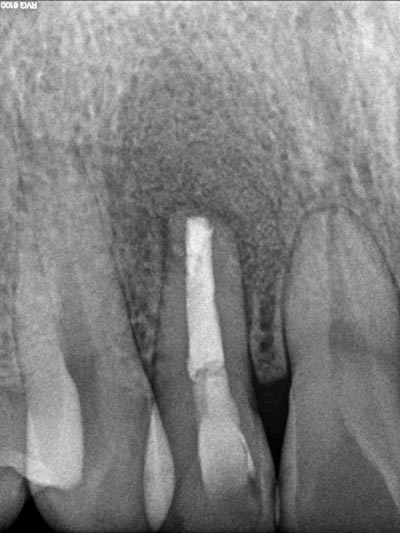

Imágenes:

Radiografía previa y final del tratamiento.

Medimos el ápice, retiramos el relleno anterior y colocamos relleno biocompatible.